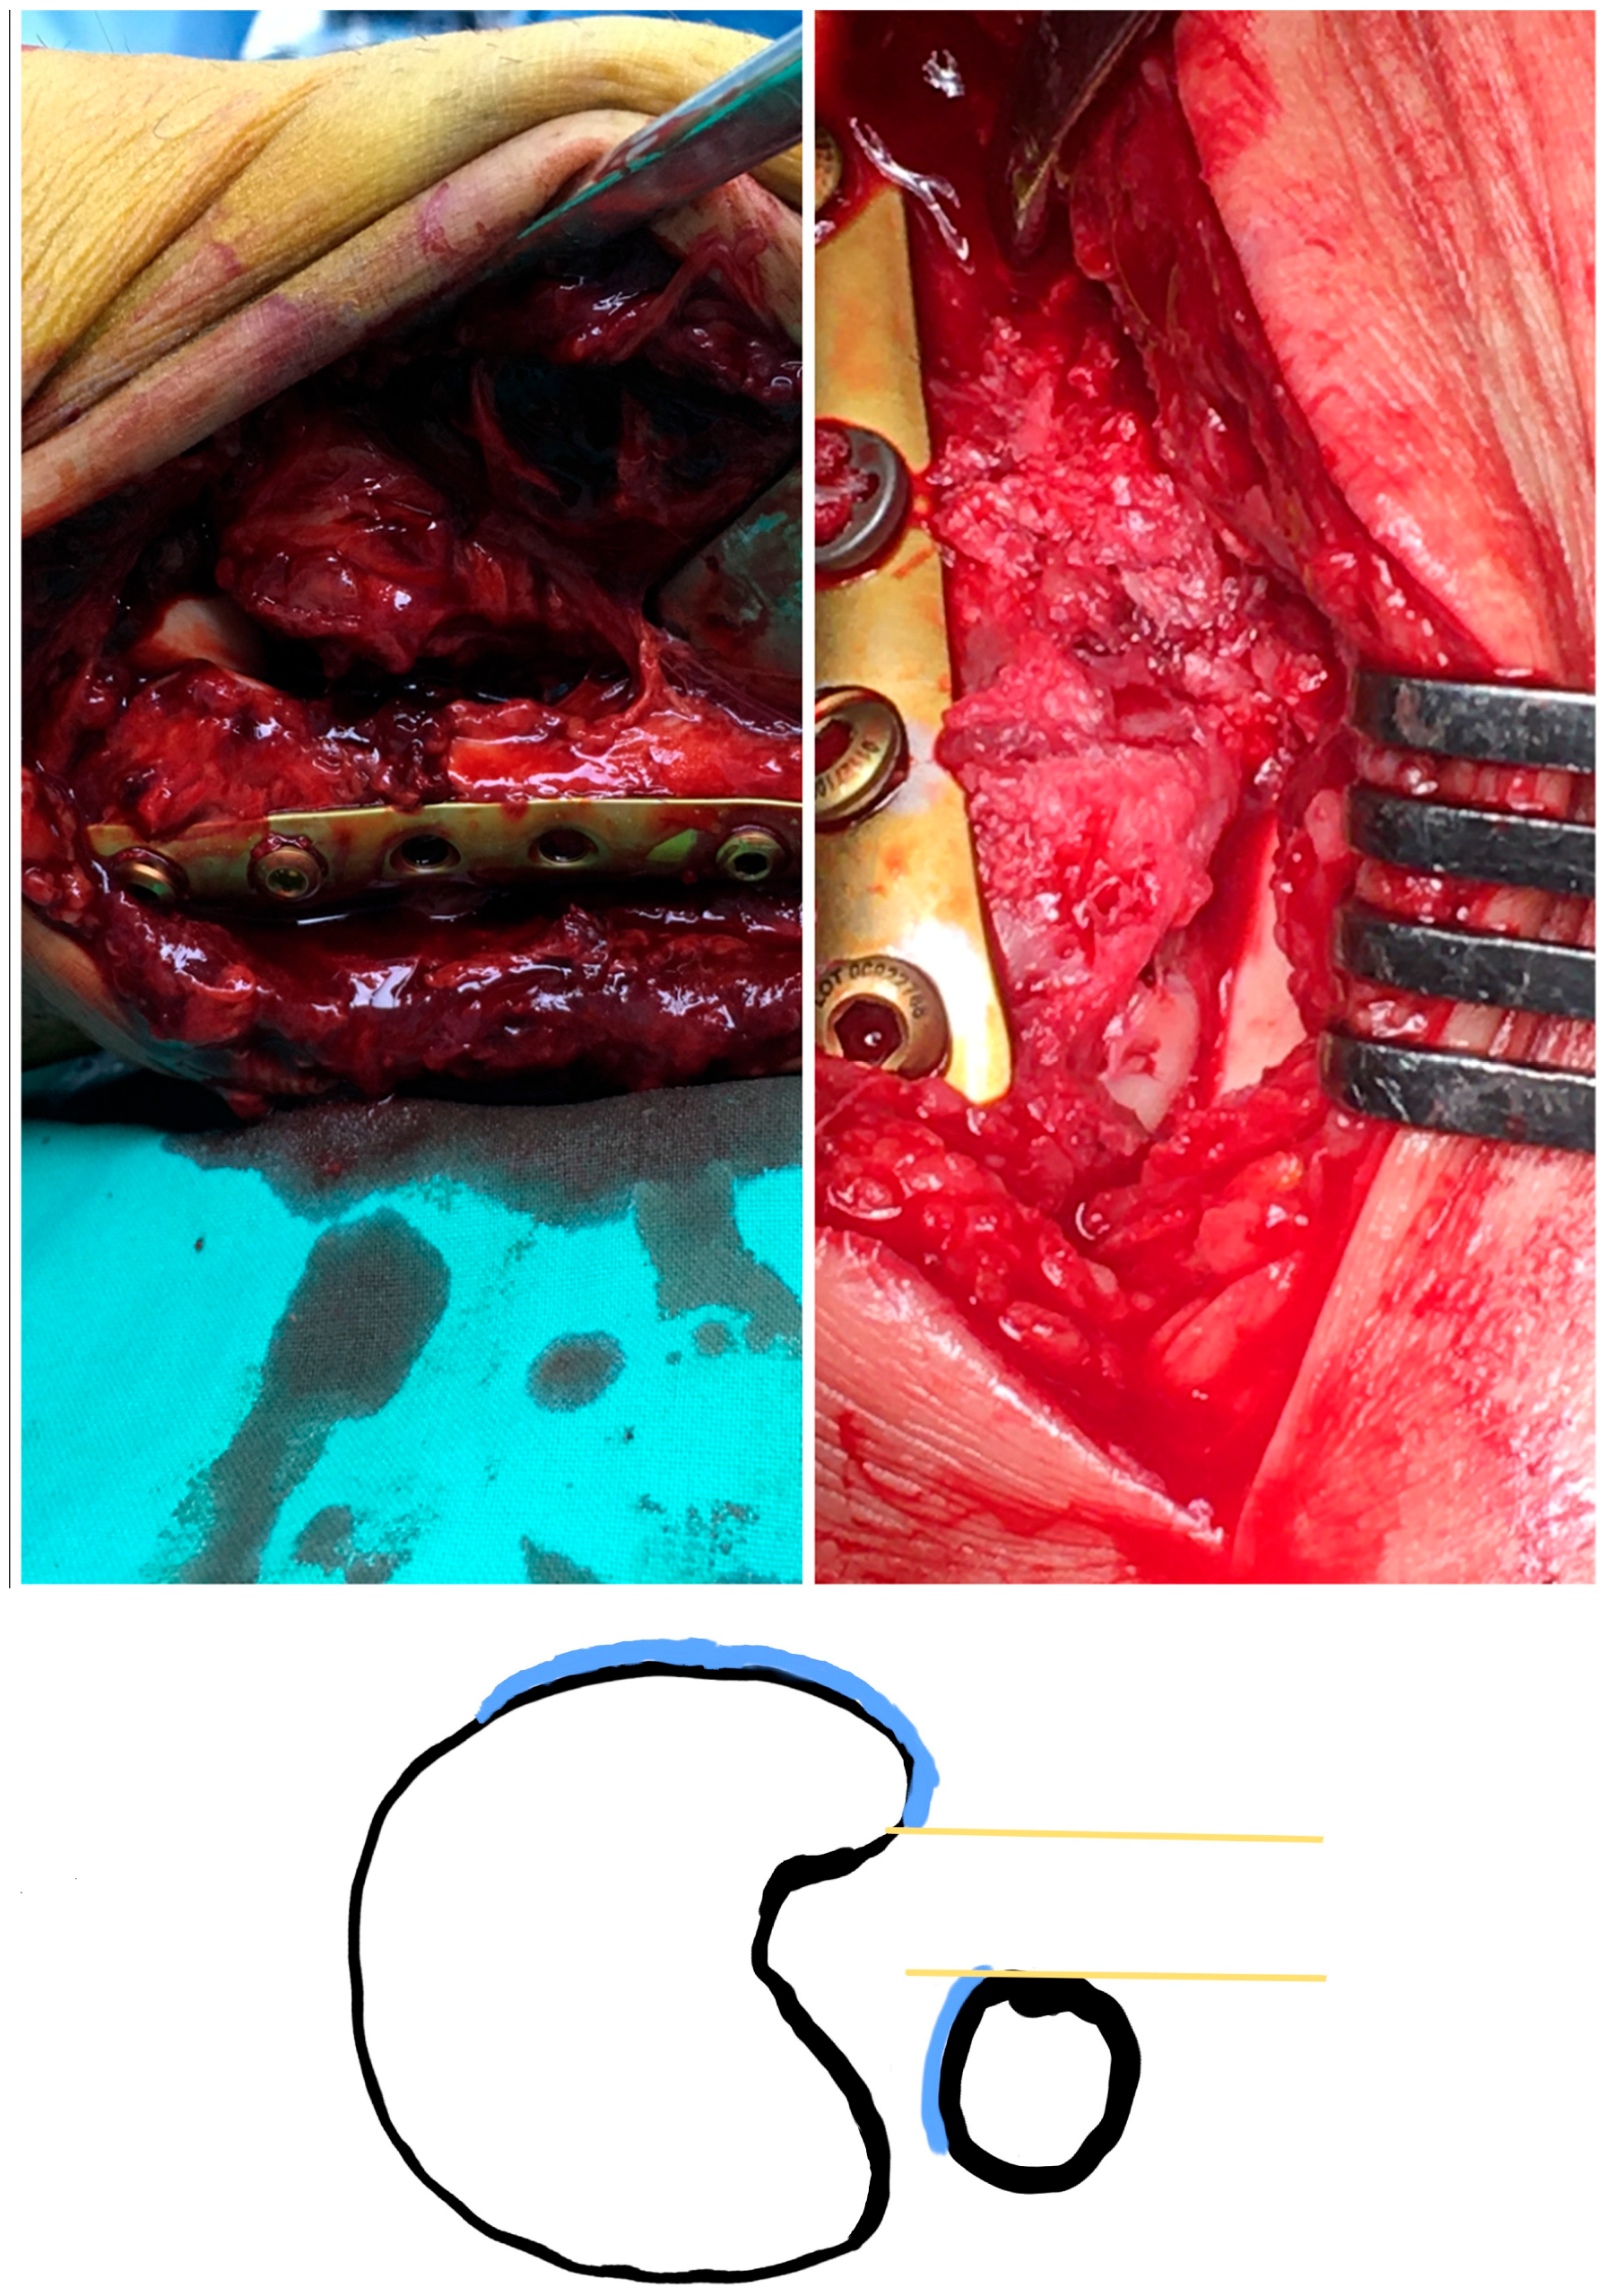

- Anatomical fixation of the fracture site

- The superior lateral malleolus cartilage was aligned with the anterolateral tibial plafond cartilage (restoring the fibula length) (Figure 2):

- The lateral malleolus cartilage was put parallel to the lateral talar surface (restoring the fibula rotation)

- In the sagittal plane, the lateral malleolus cartilage was fixed as anteriorly as the anterolateral tibial plafond cartilage (restoring the sagittal translation) (Figure 3)